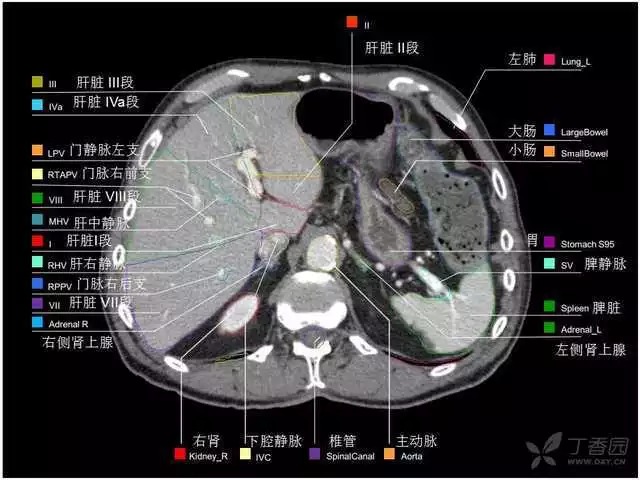

腹部肝脏高清CT断层的图谱

全腹部高清CT图谱,淋巴结彩色图谱,血管解剖图谱大汇总!